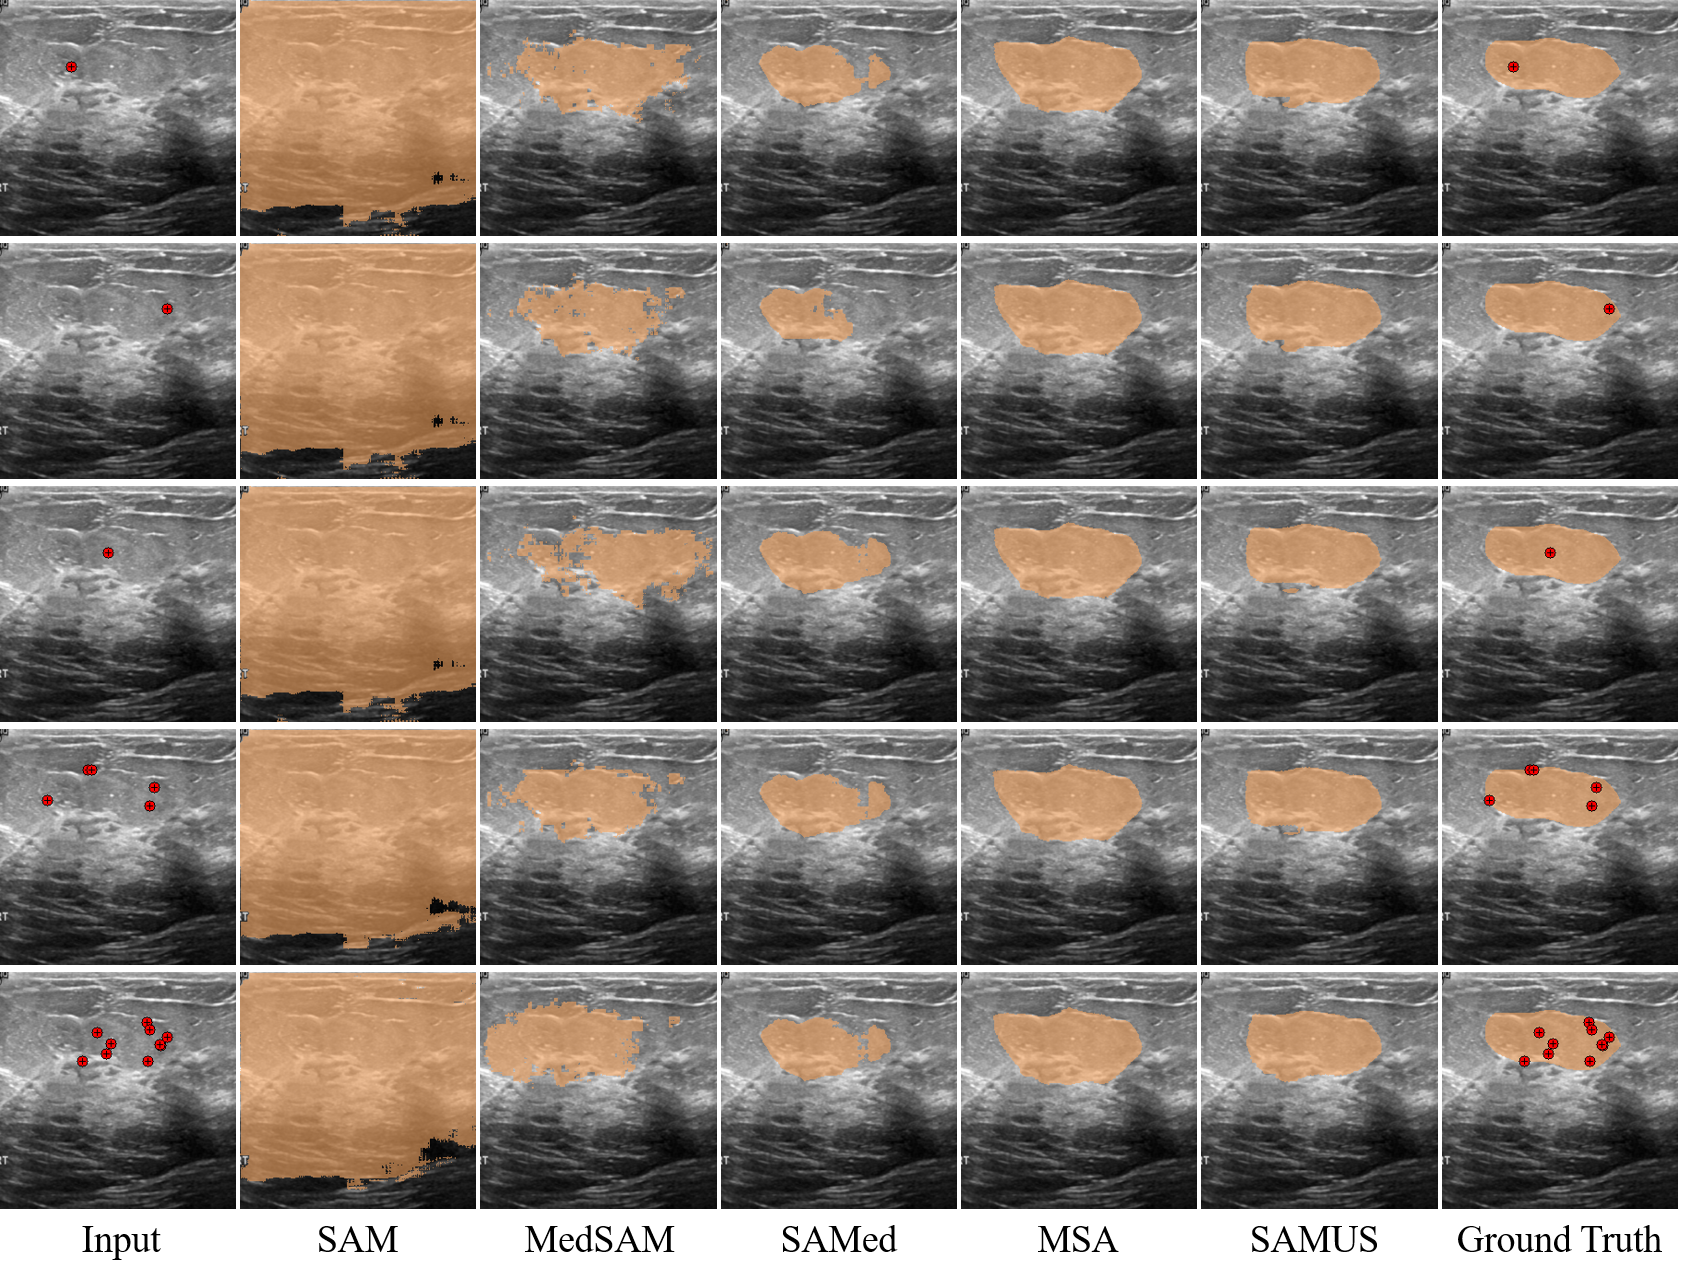

Qualitative Results on Prompts

Qualitative results of different universal models on different prompts are provided in Fig. 8. The segmentation results of SAM and MedSAM under different prompts were notably different, while the segmentation results of SAMed, MSA, and SAMUS under different prompts were relatively similar. Furthermore, SAMUS can achieve better segmentation results based on a randomly sampled single-point prompt than that of other models under a multi-point prompt.